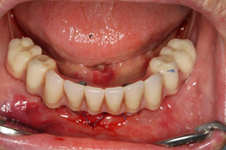

• Zavedení implantátu do kosti čelisti

Zavedení implantátů do kosti je většinou ambulantní chirurgický výkon, srovnatelný s vytržením zubu a většinou se provádí v lokální anestézii. Ve výjimečných případech je možné použít i analgosedaci či celkovou narkózu. Operaci provádí zubní lékař-implantolog při dodržení všech podmínek sterility pro operaci. Nástroje pro tuto operaci jsou konstruovány tak, aby výkon byl šetrný vůči kosti a zavedení implantátu bylo provedeno ve velmi krátké době. Díky kvalitní anestézii je výkon nebolestivý. Aby byl pooperační otok co nejmenší, je potřeba operovanou oblast chladit, dle poučení ošetřujícího lékaře. Lékař také ordinuje podle potřeby léky na bolest, případně antibiotika.